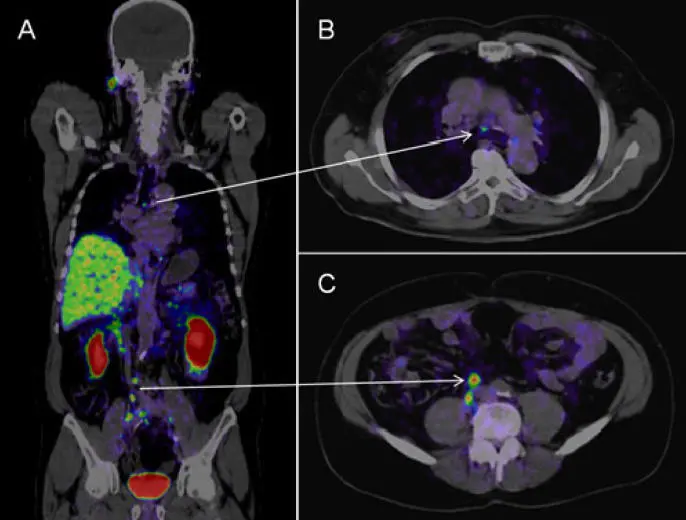

PET-CT (양전자 방출 단층촬영, PET-CT) Detects metabolically active cancer cells. (대사 활동이 활발한 암세포를 찾음.)

- Diagnosis (진단): CT, bronchoscopy, PET-CT. (CT, 기관지 내시경, PET-CT.)

CT/MRI – Staging to check for metastasis. (병기 평가 및 전이 여부 확인.)